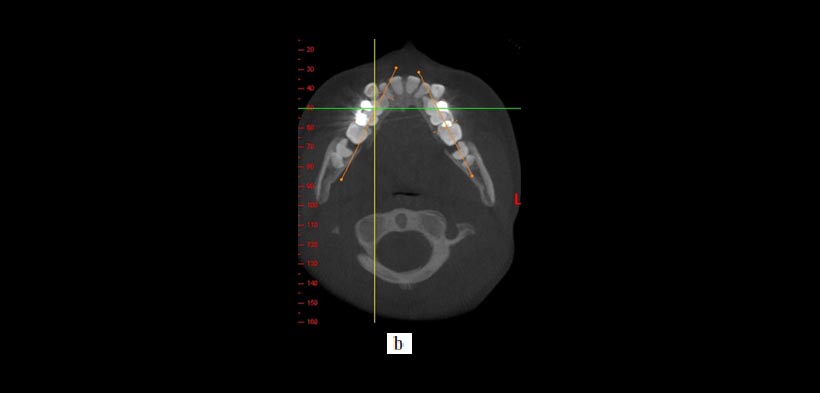

- DETERMINACIÓN ESPACIAL DE LA CORONA Y RAIZ (MORFOMETRÍA DENTOALVEOLAR): Ayuda en la determinación de las angulaciones de raíz, ofrece una evaluación precisa de la altura del hueso alveolar, sin embargo la CBCT da un número de falsos positivos en la determinación de las fenestraciones, por ende, se debe tener cuidado con respecto a la evaluación estos defectos en las imágenes (fig.2).

Figura 2. Uso de la CBCT en el diagnóstico y la planificación del tratamiento de los dientes transpuestos. Un caso que demuestra raíces transpuestas de los caninos superiores y los primeros premolares en la que la CBCT revela que la raíz canina está a vestibular de la raíz premolar. (a) Reconstrucción tridimensional y (b, c) imágenes transversales y la ubicación de la raíz. Todos estos cortes tomográficos pueden ayudar al clínico a optimizar la planificación del tratamiento.